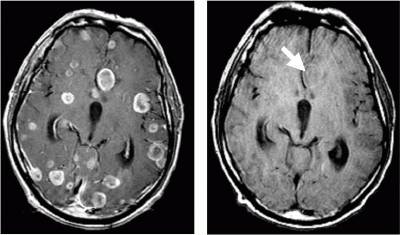

«Золотой стандарт» в диагностике метастатического рака головного мозга — магнитно-резонансная томография (МРТ). Во время этого исследования получают изображения внутренних структур тела, используя сильное магнитное поле. По снимкам врач может судить о количестве, размерах, расположении метастатических очагов.

Биопсия — исследование, во время которого получают фрагмент ткани и исследуют его на предмет раковых клеток. Если у человека уже диагностирован рак в другом органе и обнаружены очаги в головном мозге, потребности в данном методе диагностики обычно нет. Биопсия нужна, если есть очаги в мозге, но не найдена первичная опухоль.

- МРТ ‒ золотой стандарт диагностики прогрессивных раковых опухолей в этих областях. В зависимости от вида вторжения, изменяется качество изображения.

- МРТ – наиболее информативный вид диагностики для исследования метастаз.